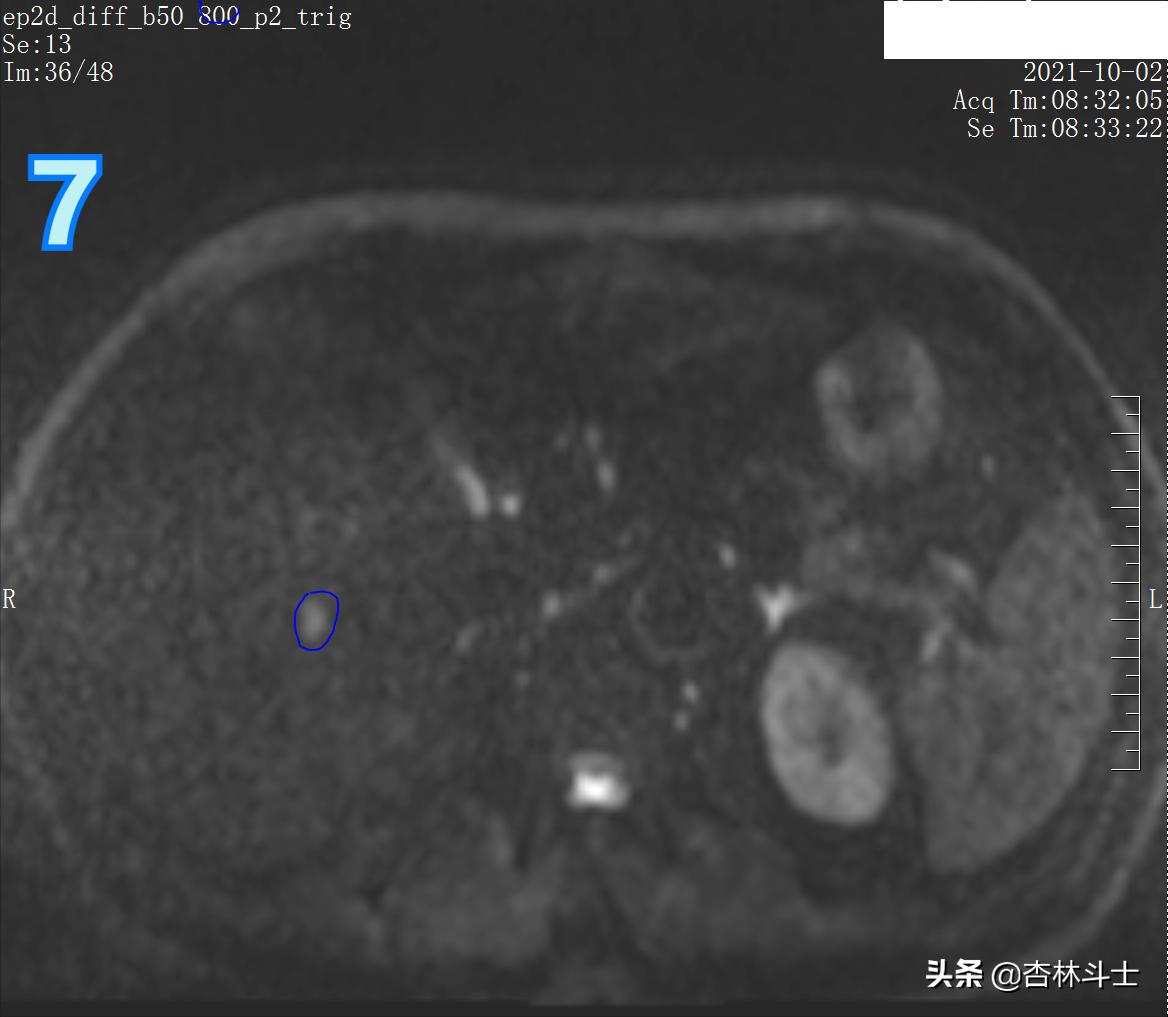

图7 DWI b800

图7 为高b值弥散加权图像(DWI),病灶呈高信号。此序列目的为了解人体内水分子“布朗运动”情况,肿瘤病灶内细胞密度高,肿瘤细胞代谢旺盛,细胞内细胞器多,细胞核大,种种原因,限制了肿瘤组织内的水分子运动,使得肿瘤病灶在DWI上呈高信号。

b值越高,越凸显身体内水分子弥散受限程度。